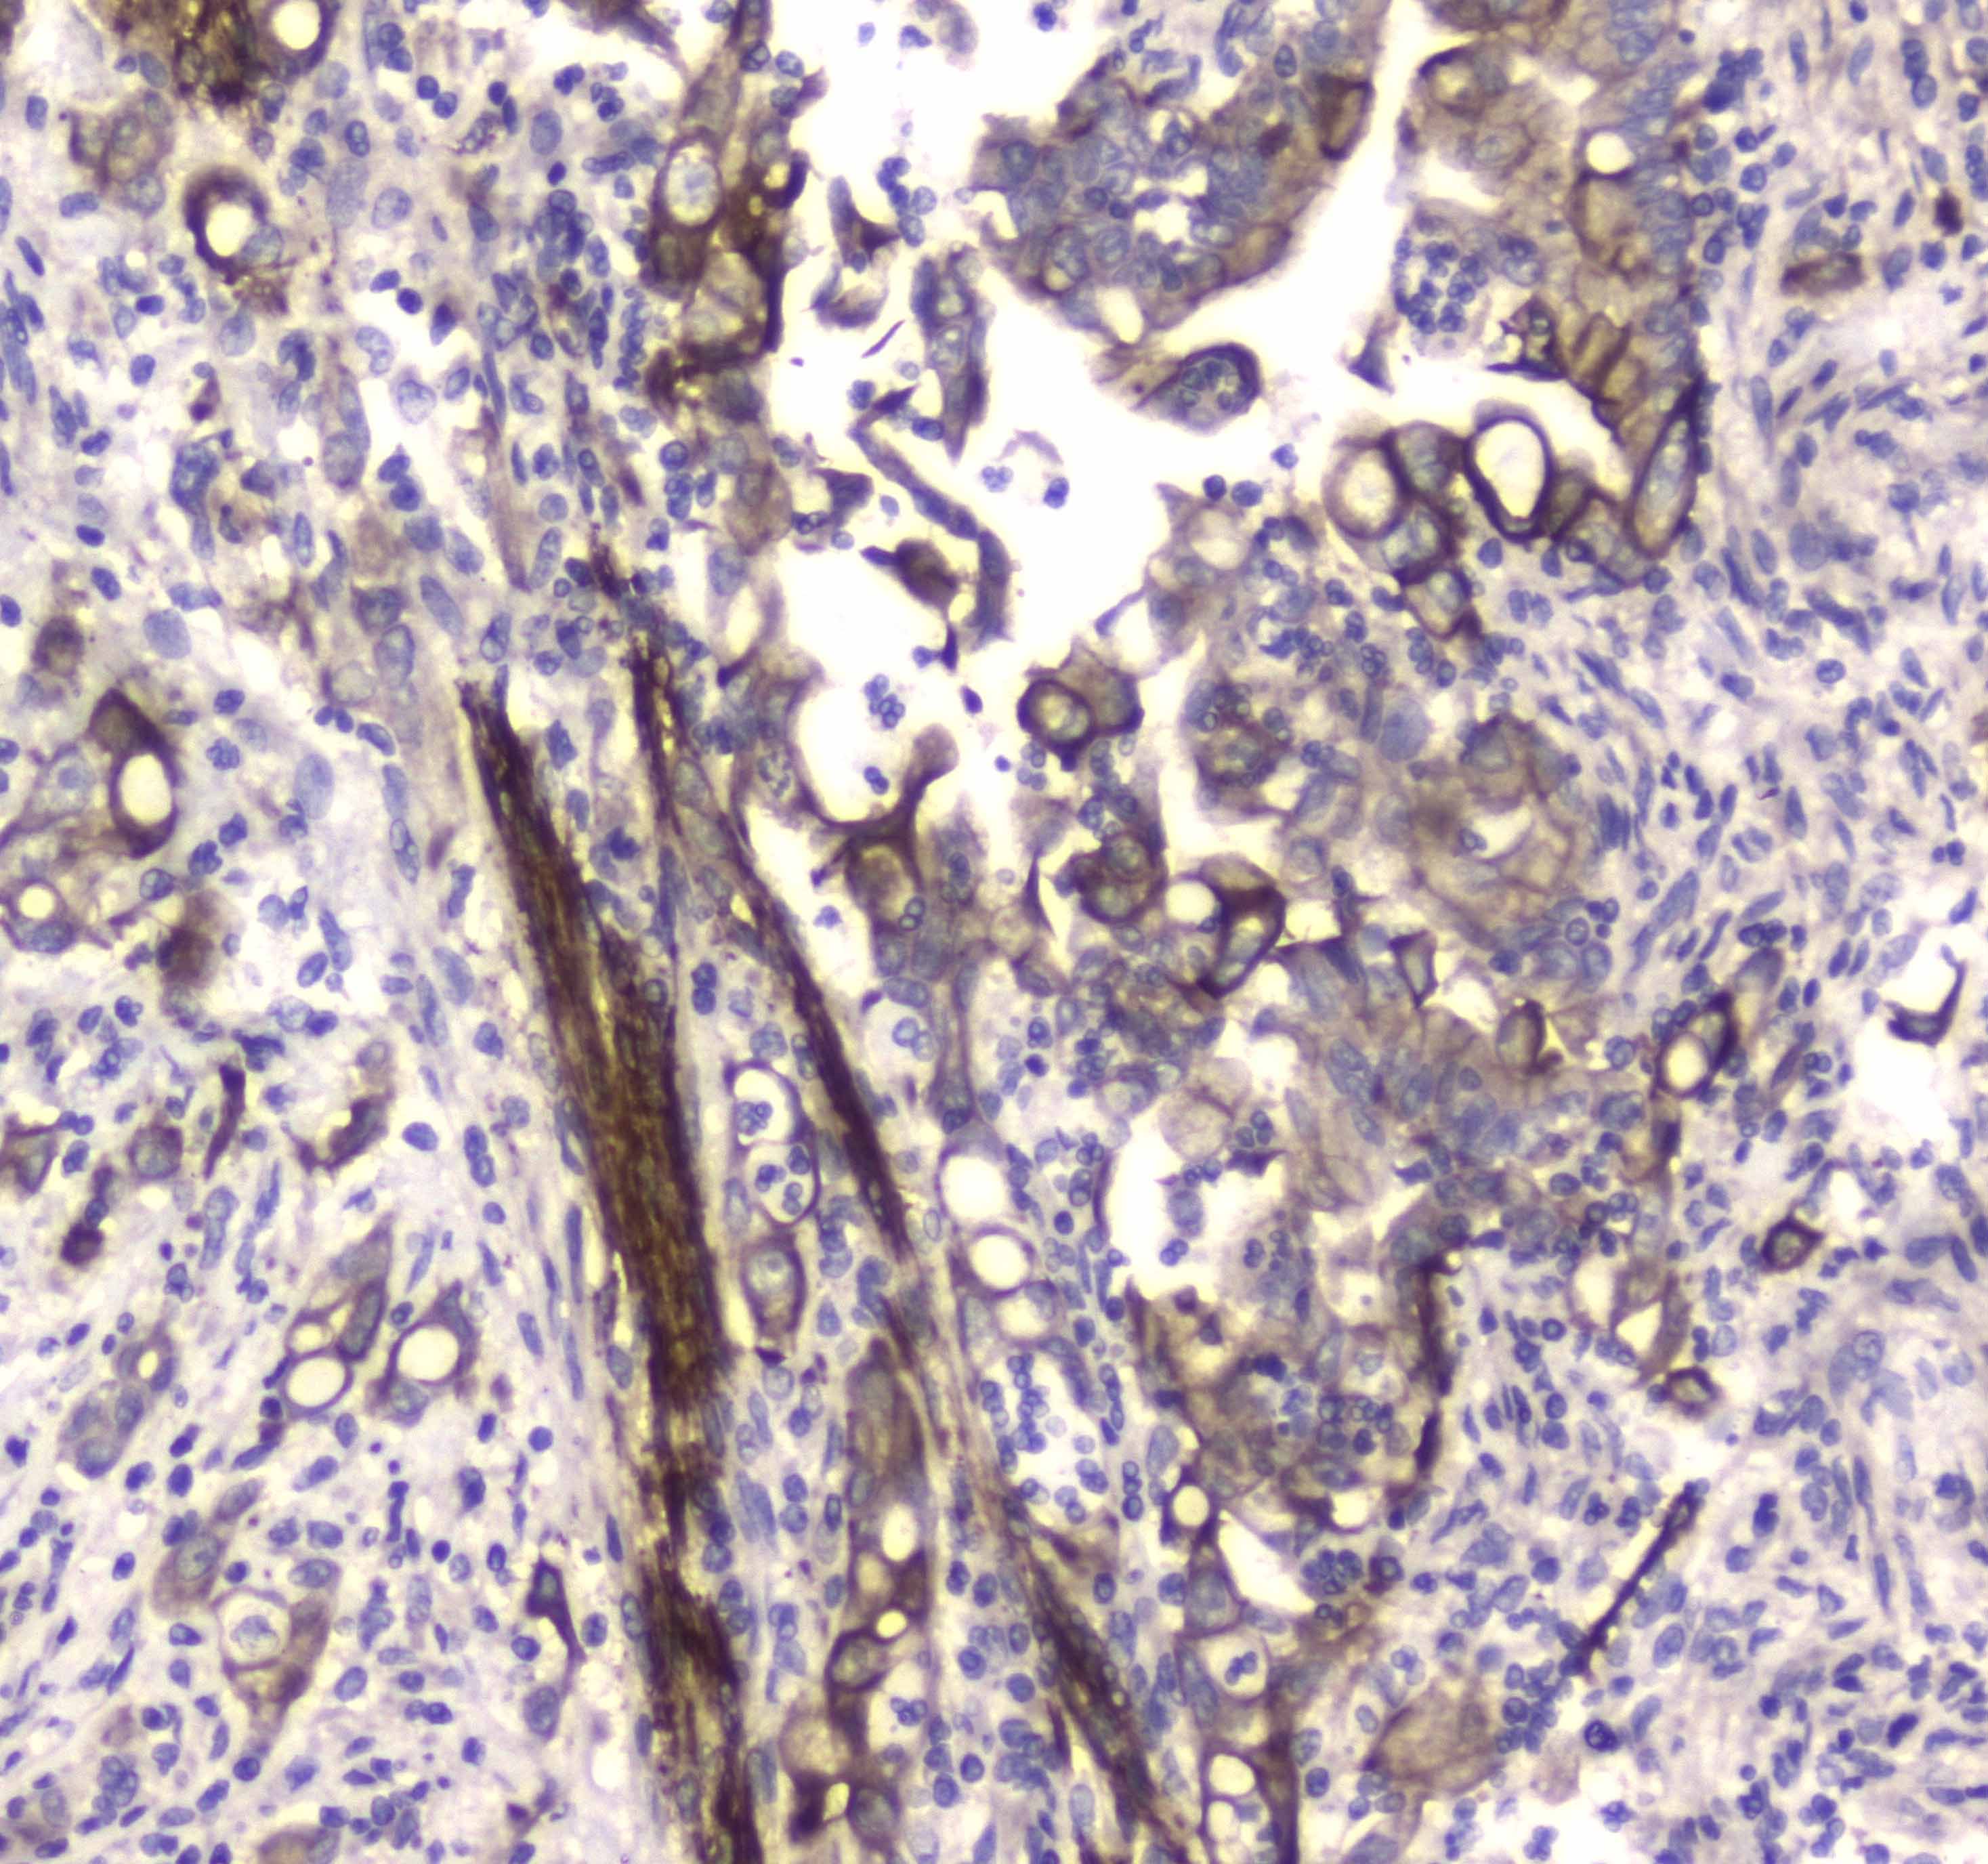

IHC analysis of LC3A/MAP1LC3A using anti-LC3A/MAP1LC3A antibody (A01543-1).

LC3A/MAP1LC3A was detected in a paraffin-embedded section of mouse brain tissue. Biotinylated goat anti-rabbit IgG was used as secondary antibody. The tissue section was incubated with rabbit anti-LC3A/MAP1LC3A Antibody (A01543-1) at a dilution of 1:200 and developed using Strepavidin-Biotin-Complex (SABC) (Catalog # SA1022) with DAB (Catalog # AR1027) as the chromogen.